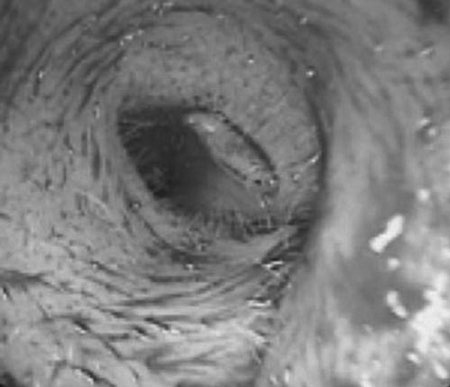

Ngày 10/12, tin từ Khoa Tai - Mũi - Họng (BV Trung ương Huế) cho biết các bác sĩ vừa thực hiện ca phẫu thuật lấy ấu trùng ruồi ra khỏi tai một bệnh nhân.

Vào ngày 8/12, bệnh nhân T.V.S. (trú xã Phong Bình, huyện Phong Điền, tỉnh Thừa Thiên – Huế) đã nhập viện ở BV Trung ương Huế với tai trái đau và nhức, có chảy dịch màu nâu hôi, riêng ống tai bị phù nề. Các bác sĩ của Khoa Tai - Mũi - Họng đã phát hiện trong tai trái của bệnh nhân S. có ấu trùng ruồi đang bò trong ống tai.

Trong tối cùng ngày 8/12, êkíp mổ gồm BS CK II Hồ Mạnh Hùng, Phó Trưởng khoa Tai - Mũi - Họng, BS CK II Đặng Như Quang (khoa Gây mê B) và BS nội trú Ngô Đức Lưu đã thực hiện ca mổ thành sau ống tai. Kết quả, ca mổ đã thành công, toàn bộ các ấu trùng ruồi đang sống được lấy hết ra khỏi tai bệnh nhân S.

Theo BS CK II Hồ Mạnh Hùng, Phó Trưởng khoa Tai – Mũi – Họng, đây là một trong những ca nhiễm trùng thuộc dạng nguy hiểm. Do ấu trùng các loại có thể tấn công từ tai vào não bộ một cách nhanh chóng cho nên nếu không phẫu thuật kịp thời, có thể ấu trùng sẽ ăn sâu vào não, dẫn đến nguy cơ tử vong cao.

Ấu trùng ruồi trong lỗ tai

Theo người nhà bệnh nhân, anh S. hiện đang qua Lào làm nghề thợ mộc ở Lào. Do tai nạn giao thông anh S. bị thương nhẹ ở vòng tai ngoài bên trái và được sơ cứu tại một cơ sở y tế. Những ngày sau, lỗ tai bệnh nhân tiếp tục đau nhức, chảy dịch nhiều. Anh S. nhập viện tiếp thì các BS đã lấy ra được 80 ấu trùng ruồi. Nhưng do vẫn đau nhức ở tai trái nên buộc phải chuyển vào BV Trung ương Huế.

Hiện bệnh nhân đang được điều trị bằng thuốc kháng sinh để ngăn chặn trứng ruồi nở, phát triển trong lỗ tai.